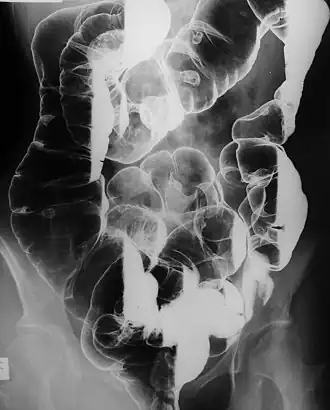

![]() Множественные полипы в толстой кишке | |

Вторым специфичным признаком являются множественные полипы в желудочно-кишечном тракте. Они проявляются болями в животе, желудочными и кишечными кровотечениями (в результате чего появляется кровь в кале и развивается анемия), инвагинация кишечника и острая кишечная непроходимость.